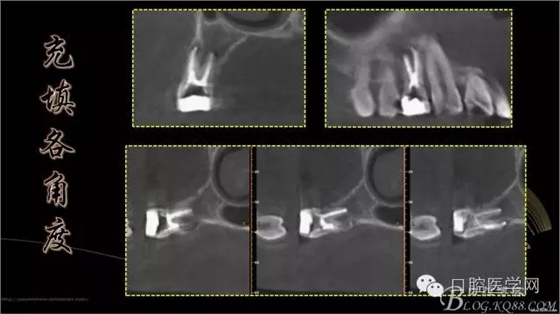

首頁(yè)牙體牙髓 上頜第一前磨牙3根管

上頜第一前磨牙3根管